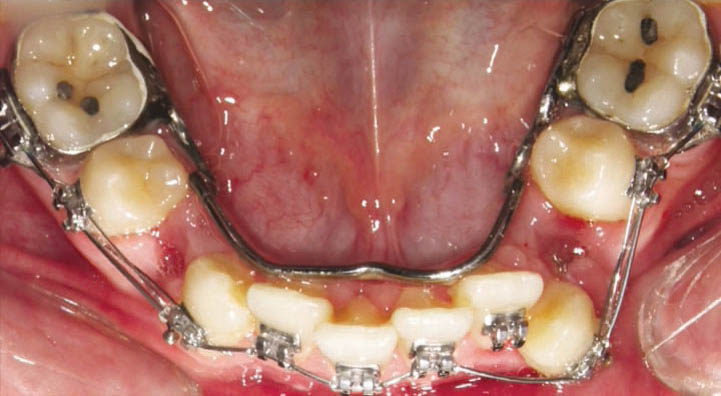

در سمت مزیال و دیستال مولر یک عدد آن را بگذارید تا بعد از یک هفته نقطه تماس باز شود. یک سمت سپراتور زیر کنتاکت و سمت دیگر بالای کنتاکت باید باشد (شکل 58-1) برای دندانهای قدامی هم سپراتور داریم که کوچکتر از خلفیها میباشند و در زمان استریپ قدامیها با فرز یا دیسک، باید از آنها استفاده کنیم تا نقطه تماس باز شود بعد استریپ کنیم.

اگر نیاز به ساختن لینگوال آرچ یا پالاتالبار دارید (مثلاً برای جلوگیری از حرکت مزیالی مولرها و حفظ فضای E) باید بندها را در جایگاه خود بگذارید و با گیج ارتفاع آن را تنظیم کنید، بعد یک قالب pick-up از روی آنها با آلژینات میگیرید. سپس بندها را خارج و درون آلژینات میگذاریم (شکل 60-1) و گچ آن را میریزیم. بدینصورت بندها به روی کست گچی منتقل میشوند. حال این قالب را به لابراتوار بفرستید تا پالاتالبار یا لینگوال آرچ بسازند. بهتر است بندها را یک درجه بزرگتر بگیرید تا زمانی که به یکدیگر لحیم میشوند جازدن روی دندانها مشکل نشود.

برای ساختن پالاتالبار (شکل 61-1) بهتر است از سیم 1.2mm استفاده نمائید ولی برای ساختن لینگوال آرچ (شکل 62-1) سیم 1mm هم کافی میباشد. این سیم بندهای مولراول را بههم متصل میکند و دارای لوپی هستند که انعطاف پذیری آن را بیشتر میکند.

شکل 62-1: لینگوال آرچ